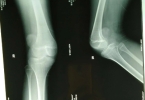

磁共振成像检查是诊断股骨头坏死的金标准,是对股骨头坏死早期诊断最敏感的有效无创检查MRI的T1WI显示带状低信号或T2WI在显示双线征时,可以诊断股骨头坏死,因此一般可以检查股骨头坏死的磁共振成像。

对于CT检查可以清楚地显示软骨下骨板断裂、坏死炉的范围和修复情况。骨硬化带通常包裹坏死骨,修复骨,或软骨下骨断裂,或诊断股骨头坏死。

此外,股骨头坏死也可以通过X线检查,CT检查和其他检查被诊断出来。对于X线检查,一般采用双髋正位和蛙式位片,可诊断新月征、坏死灶被硬化骨包围或分段塌陷。